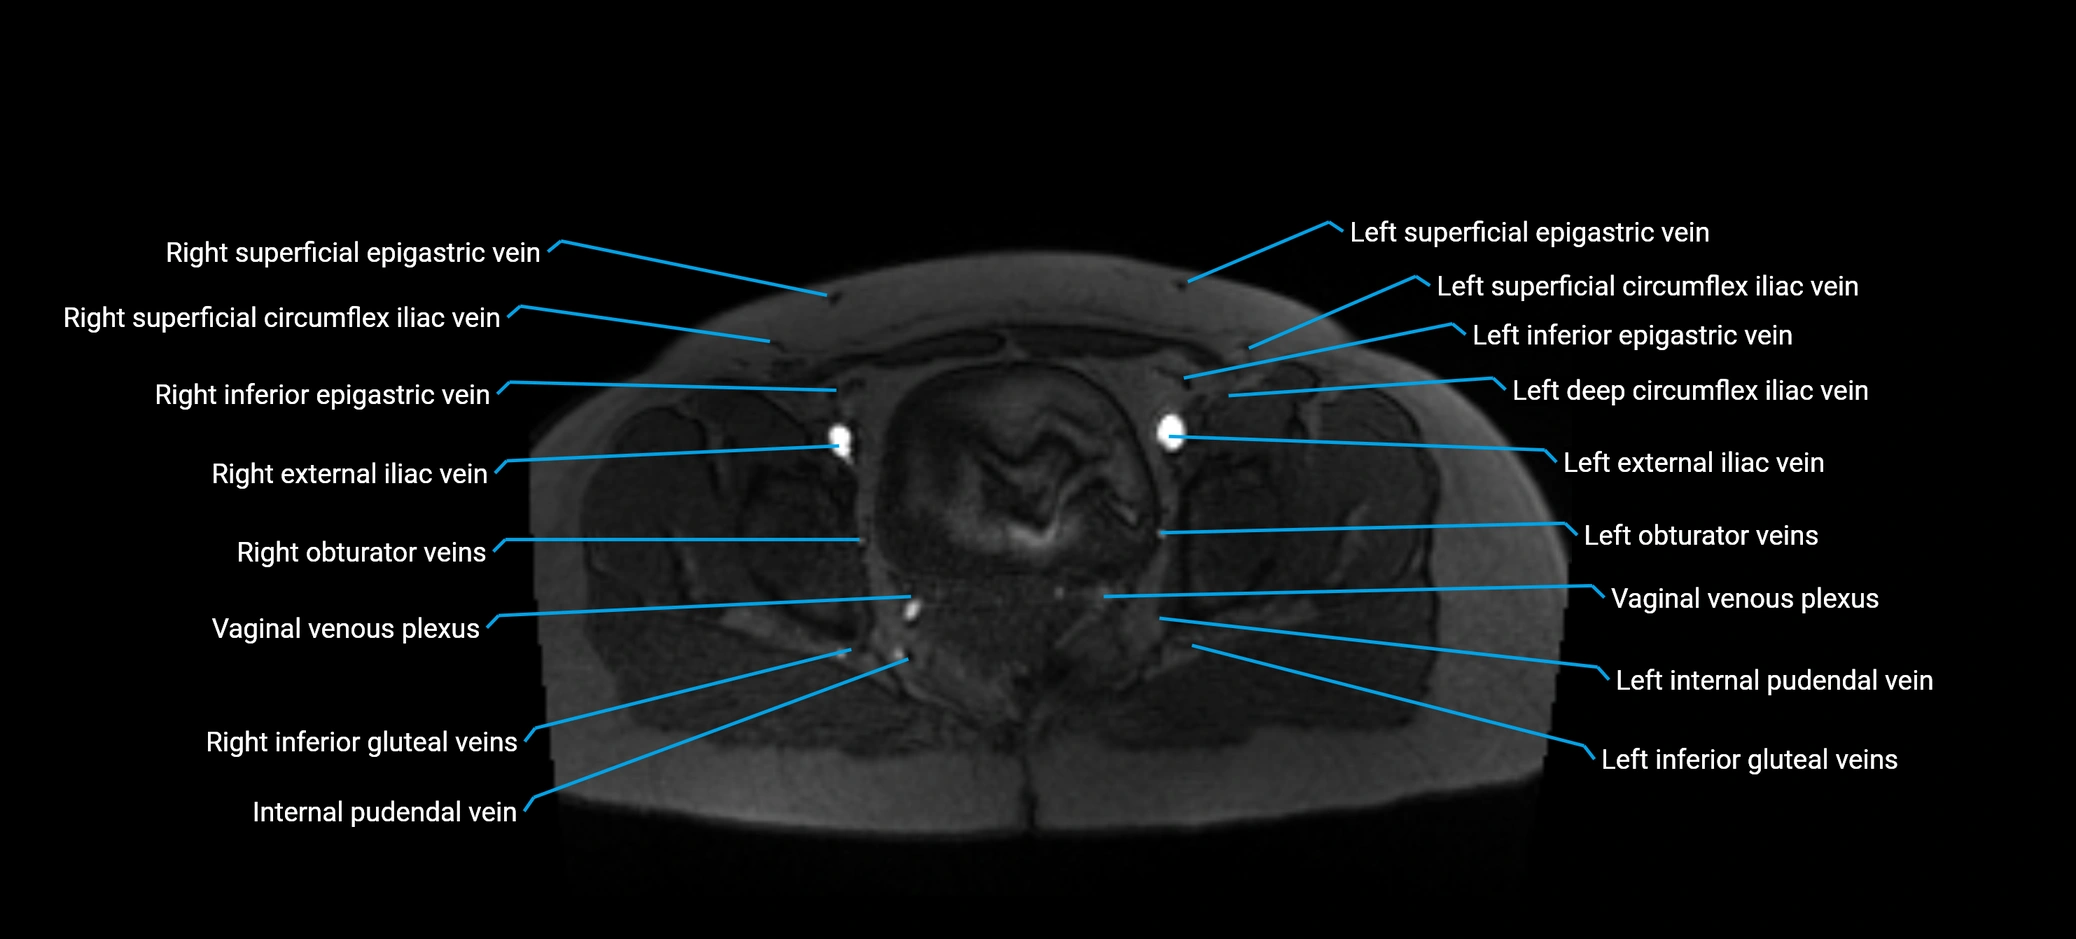

MRI image

image